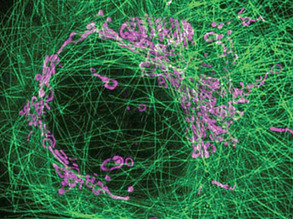

Targeting Malaria

10